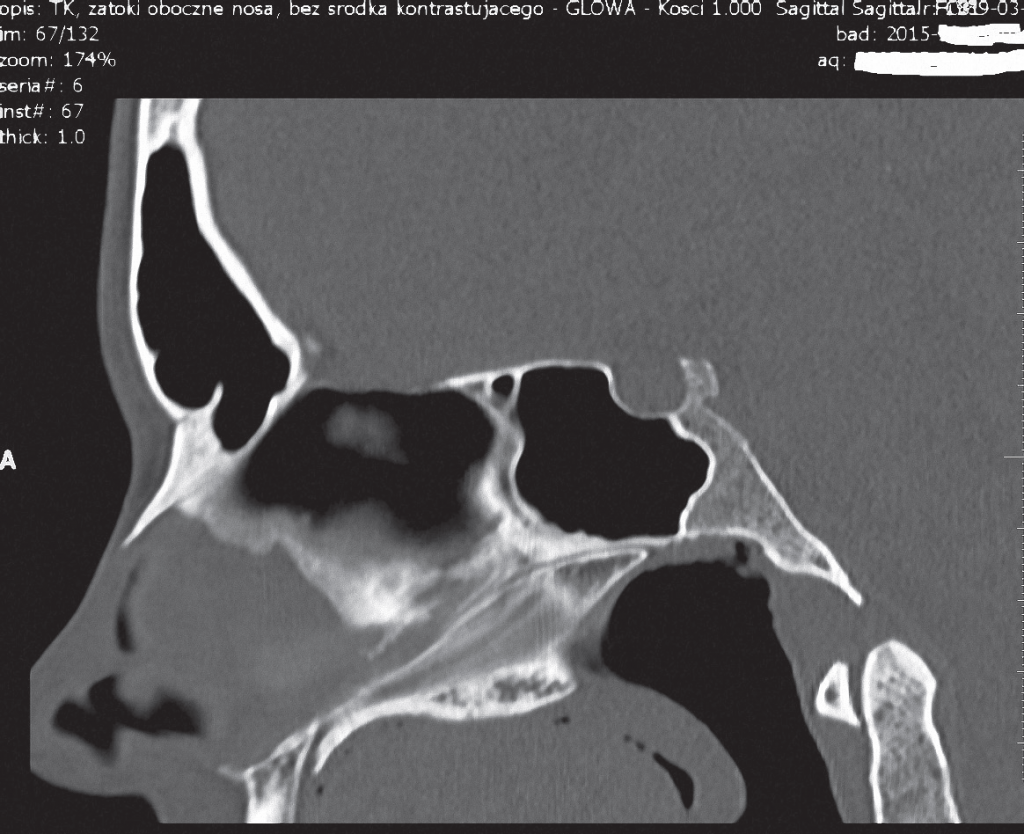

Streszczenie: Drożny przewód nosowo-podniebienny jest rzadką anomalią zlokalizowaną w przedniej części kości szczęki. Przetrwały przewód nosowo-podniebienny jest uważany za wadę rozwojową. Na ogół prezentuje się jako jeden lub dwa małe otwory bocznie lub tylne w stosunku do brodawki przysiecznej. U pacjentów objawia się to dziwnymi uczuciami, takimi jak piskliwy lub skrzekliwy dźwięk, wysuszone podniebienie, cofanie się wydzieliny z nosa, drogą oddechową pomiędzy jamą ustną i nosową. Ból tej okolicy należy jednak do rzadkości. Opis przypadku przedstawia 27-letnią kobietę z drożnym przewodem nosowo-podniebiennym.

- Opis przypadku przedstawia 27-letnią kobietę z drożnym przewodem nosowo-podniebiennym.